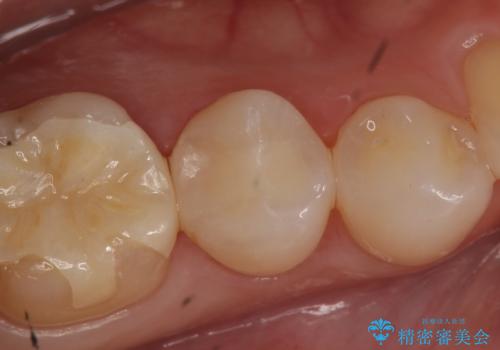

- 右下5番目の歯がしみるので診て欲しいといらっしゃった方の症例です。

虫歯を除去後、セラミックインレーによる修復を行いました。

当院のセラミックインレーはemaxという強度と審美性に優れた材料を使用しています。

またプレス方式でインレーを製作しているため、削り出しで製作するCADCAMより優れた適合性も持ち合わせており、虫歯が再発しにくい修復物です。